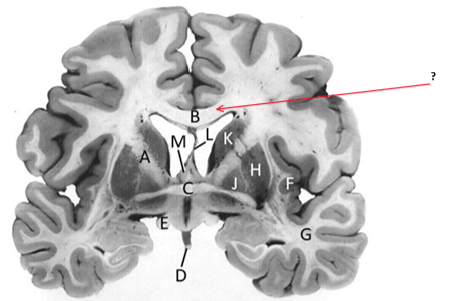

Name this and state its function.

Corpus Callosum.

Putamen.

Name this, state its function, pathways and cellular components.[5 marks]

Caudate nucleus.

Medium spiny neurons utilising GABA and some Cholinergic.

From cortex–>CN–>hippocampus, Gp and thalamus.

Septum pellucidum.

Fornix.

Anterior commissure.

Interconnects:

Infundibular stalk.

Insula.

Name this, state its function, components[2] and the difference in pathways.

Internal capsule.

Anterior limb:

Posterior limb:

Corticospinal tracts and corticopontine tracts: